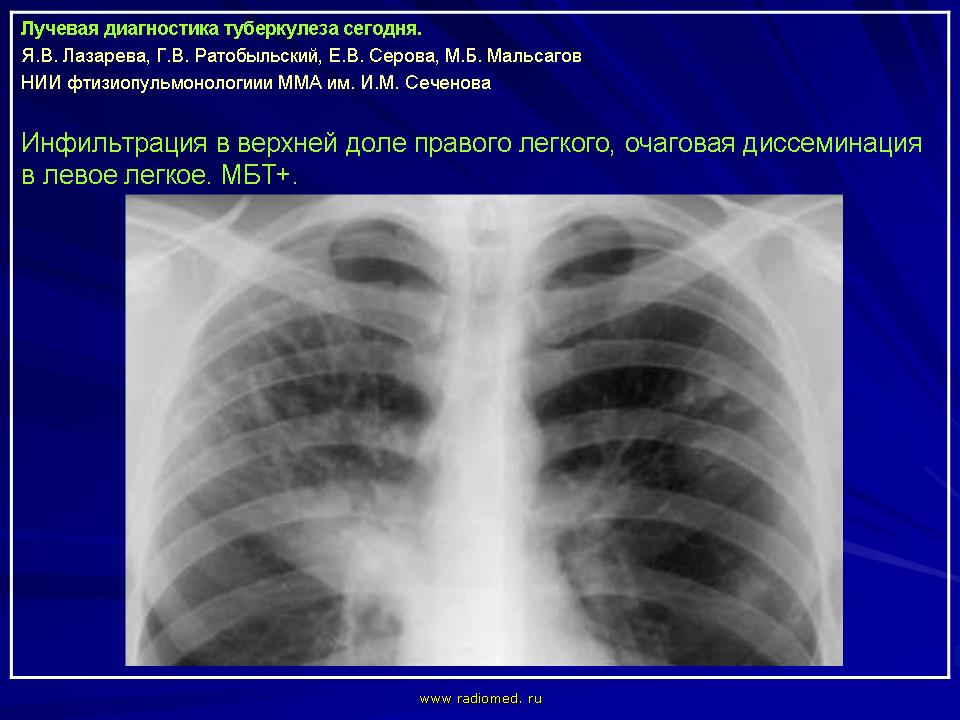

Лучевая диагностика туберкулеза сегодня

Я.В. Лазарева, Г.В. Ратобыльский, Е.В. Серова, М.Б. Мальсагов

НИИ фтизиопульмонологиии ММА им. И.М. Сеченова